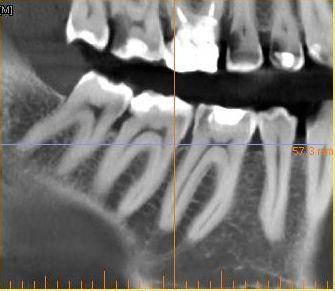

Интересовала в частности развалившаяся 6-ка сверху.

уже давно леченная -перелеченная.

Вердикт -надо кроме нее удалить также и 4 и 5 рядом стоящие - типа киста.

По поводу 6 ки я еще готов удалить так как там похоже невозможно что-то сделать но 4-ка с 5-кой свиду не такие плохие. возможно их перелечить ?

Отскринте нормально снимок: чтобы полностью было видно и корни зубов!

Добрый вечер, может опять не так сделал?

tecom, нормально! А вот на 4 и 5 кисты нет! Но лечить зубов очень много: практически каждый...

Плюс ещё пародонтит в том числе на 4 и 5...